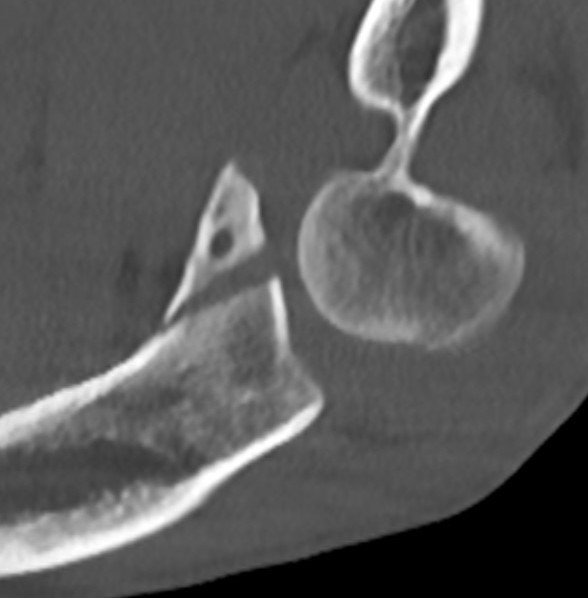

Elbow dislocation with radial head fracture

Management

Critical to elbow stability

Based upon Mason classfication